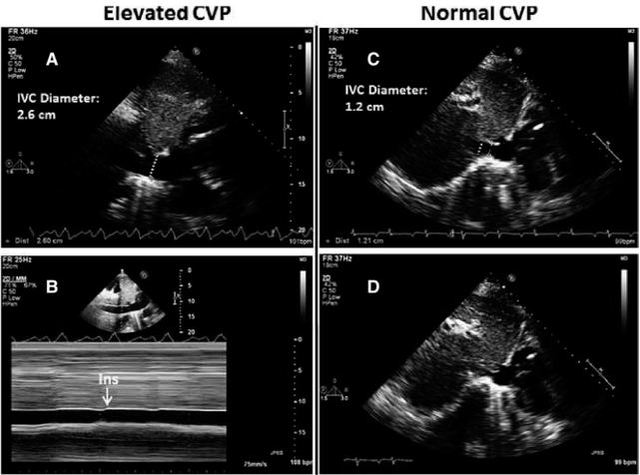

2019-03-14 08:16 664 血容量不足 超声心动图 组织多普勒 中心静脉压 肺动脉压 肺毛细血管楔压 心输出量 最新资讯 经典病例 临床综述 利尿剂

了一例通过超声心动图评估血流动力学并指导诊疗的病例,